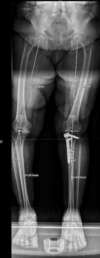

Arthrose médiale des 2 genoux avec grande déformation en varus

même patiente après chirurgie côté gauche : ostéotomie, et plaque + greffe en place